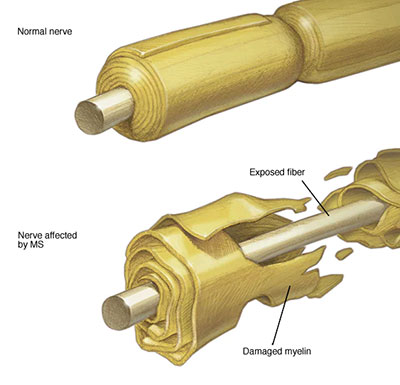

در بیماری ام اس ، سیستم ایمنی بدن به غلاف محافظ (میلین) حمله می کند که فیبرهای عصبی را می پوشاند و باعث ایجاد مشکلات ارتباطی بین مغز و بقیه بدن می شود. در نهایت ، این بیماری می تواند باعث آسیب دائمی یا خرابی اعصاب شود.

علت این بیماری ناشناخته است. این یک بیماری خود ایمنی است که در آن سیستم ایمنی بدن به بافتهای خود حمله می کند. در مورد ام اس ، این عملکرد نادرست در سیستم ایمنی باعث از بین رفتن ماده چربی پوشاننده و محافظت از رشته های عصبی مغز و نخاع (میلین) می شود.

میلین را می توان با پوشش عایق سیمهای الکتریکی مقایسه کرد.

هنگامی که میلین محافظ آسیب دیده و فیبر عصبی در معرض آن قرار می گیرد ، پیام هایی که در امتداد آن فیبر عصبی حرکت می کنند ممکن است کند و یا مسدود شوند.